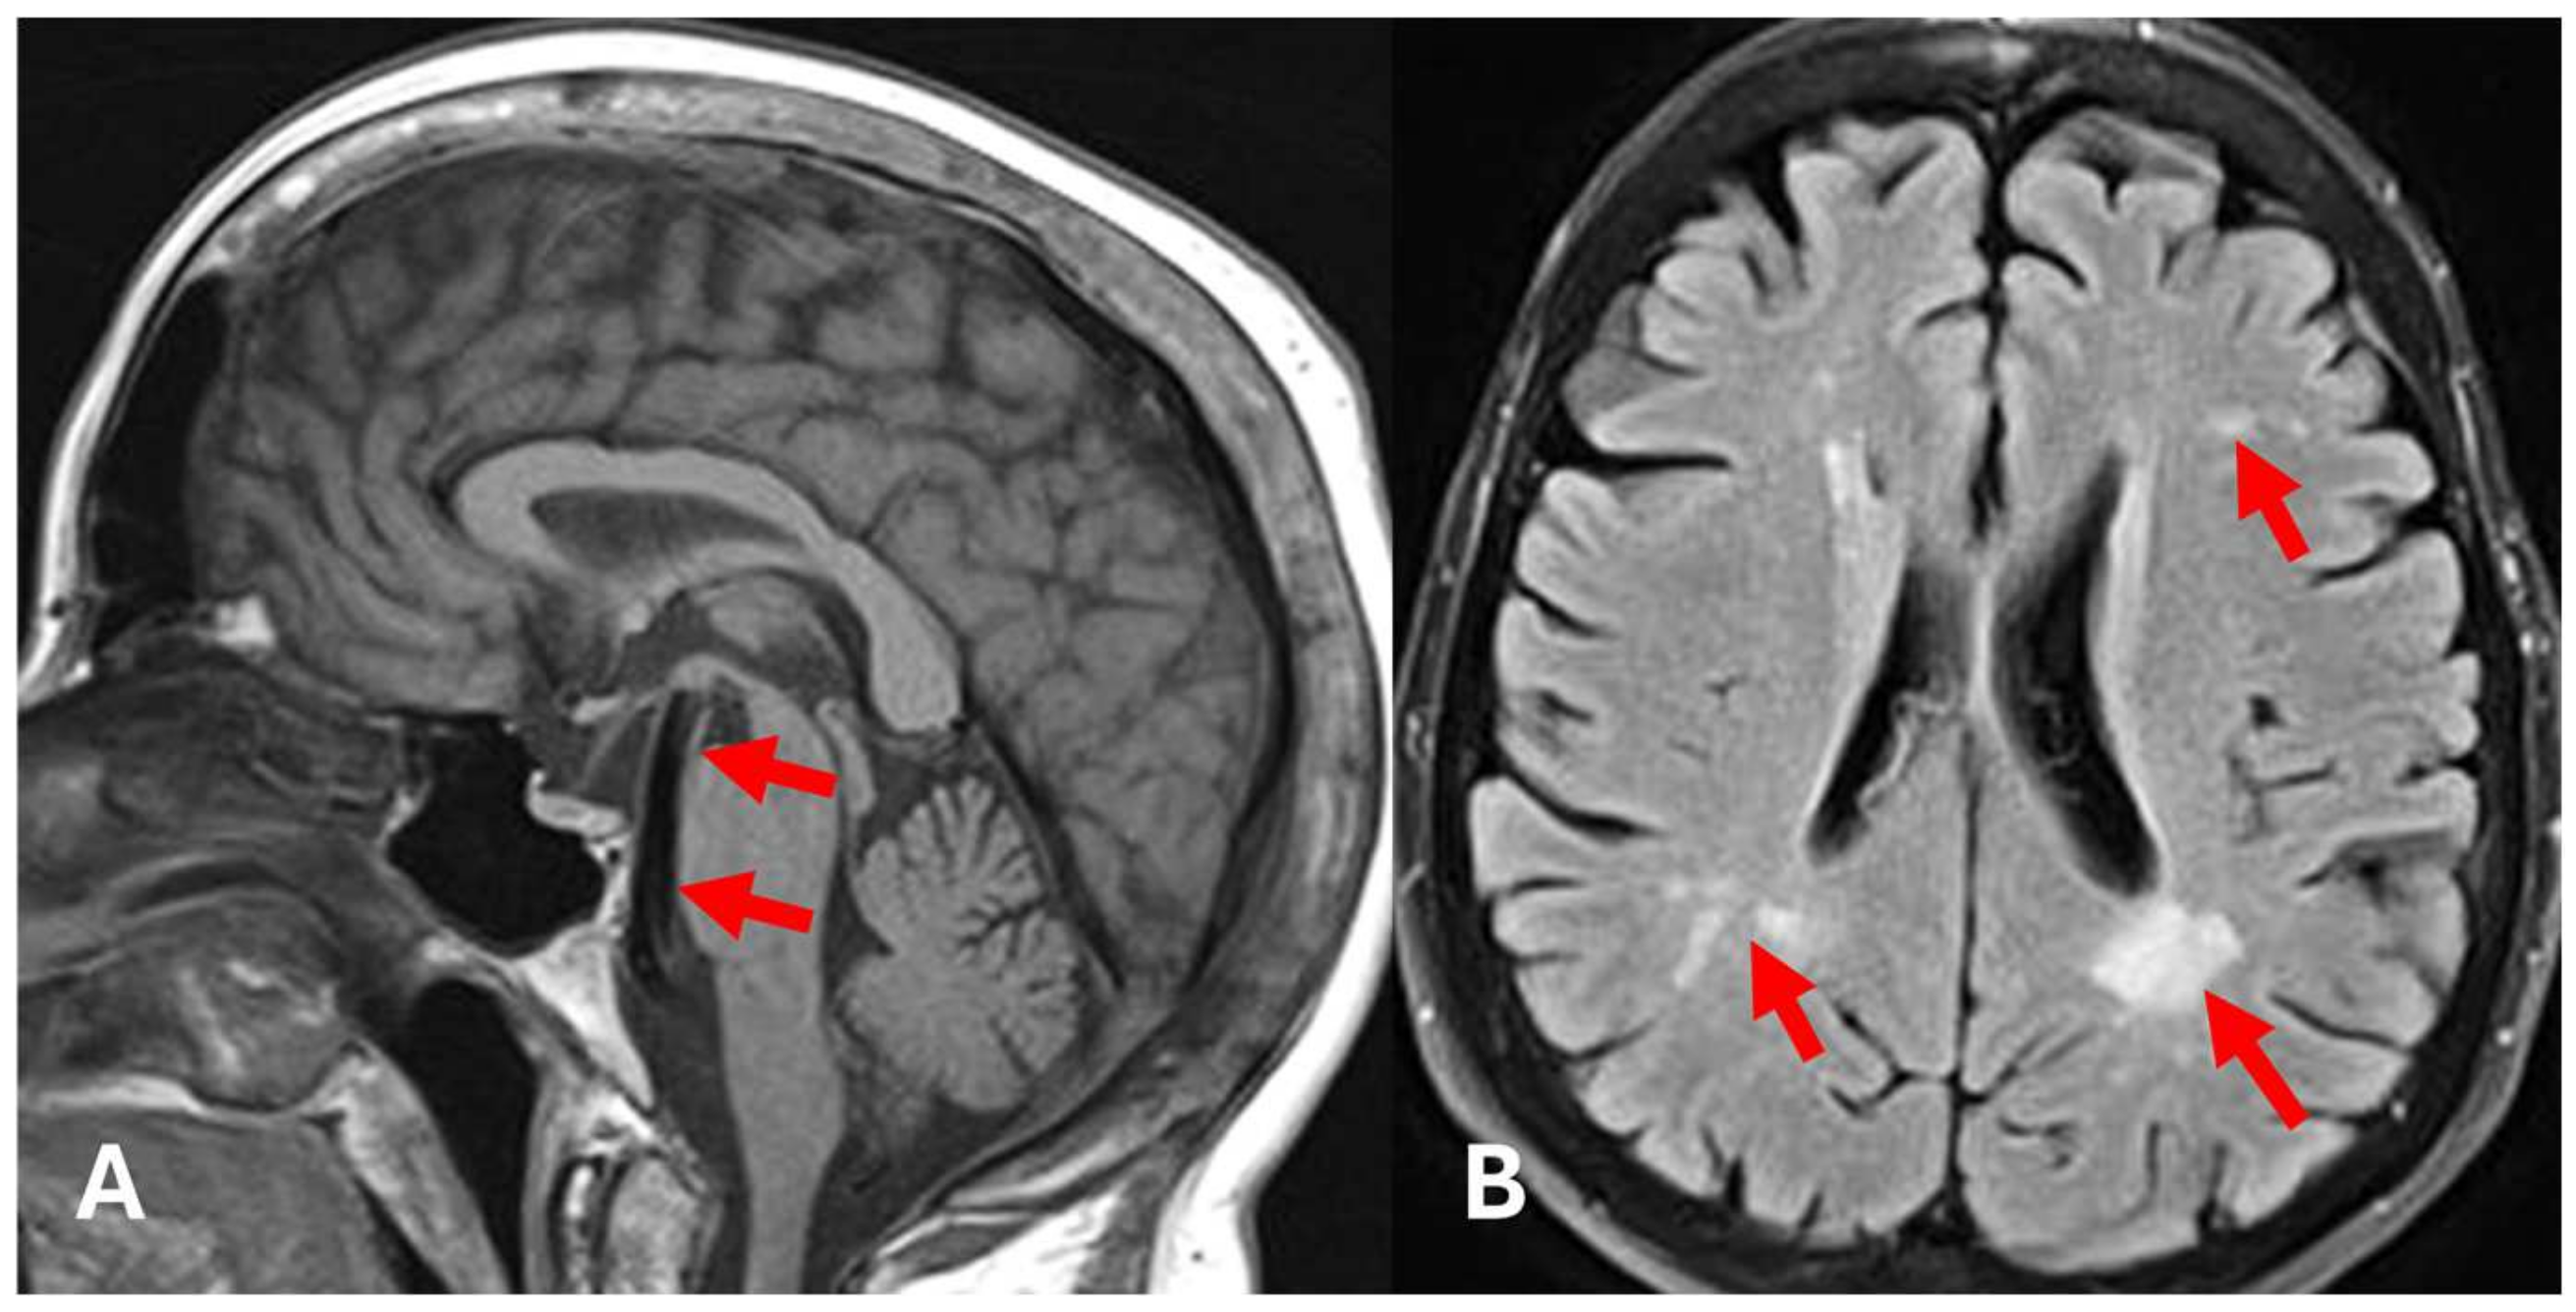

2. Case Presentation